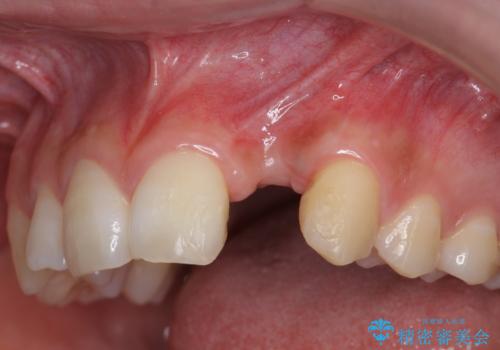

- [ 再生治療・歯周外科・小矯正・セラミック補綴 ] 前歯の歯周病治療- 担当医 大元洋佑 ![[ 再生治療・歯周外科・小矯正・セラミック補綴 ]  前歯の歯周病治療の症例 治療前](https://seimitsushinbi.jp/wp/wp-content/uploads/2022/12/83065c2454a29ed71cf190e15a6106f4-500x350.jpg?v=1671673398) ![[ 再生治療・歯周外科・小矯正・セラミック補綴 ]  前歯の歯周病治療の症例 治療後](https://seimitsushinbi.jp/wp/wp-content/uploads/2022/12/ec16e37ee53325a6f6629b94759f5513-500x350.jpg?v=1671673454)